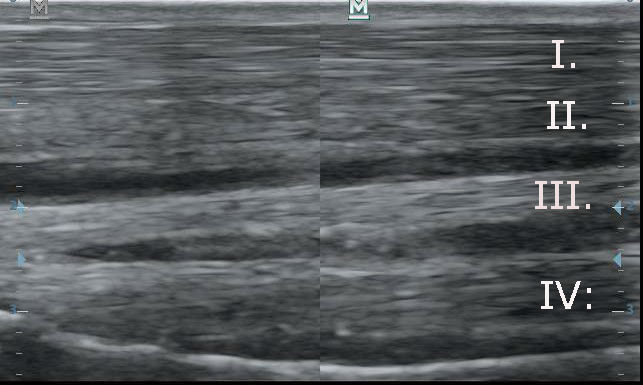

Az első képen hosszmetszetben láthatóak az inak. Rostjaik szabályosan lefutó erős, fehér csíkok. A második képen keresztmetszetben láthatóak az inak. Rostjaik erős, fehér pöttyök. A négy ín fentről lefelé: I. Felületes ujjhajlító ín. I.: Mély ujjhajlító ín. III. Járulékos szalag. IV. Egyenítő szalag (Suspensory ligament)